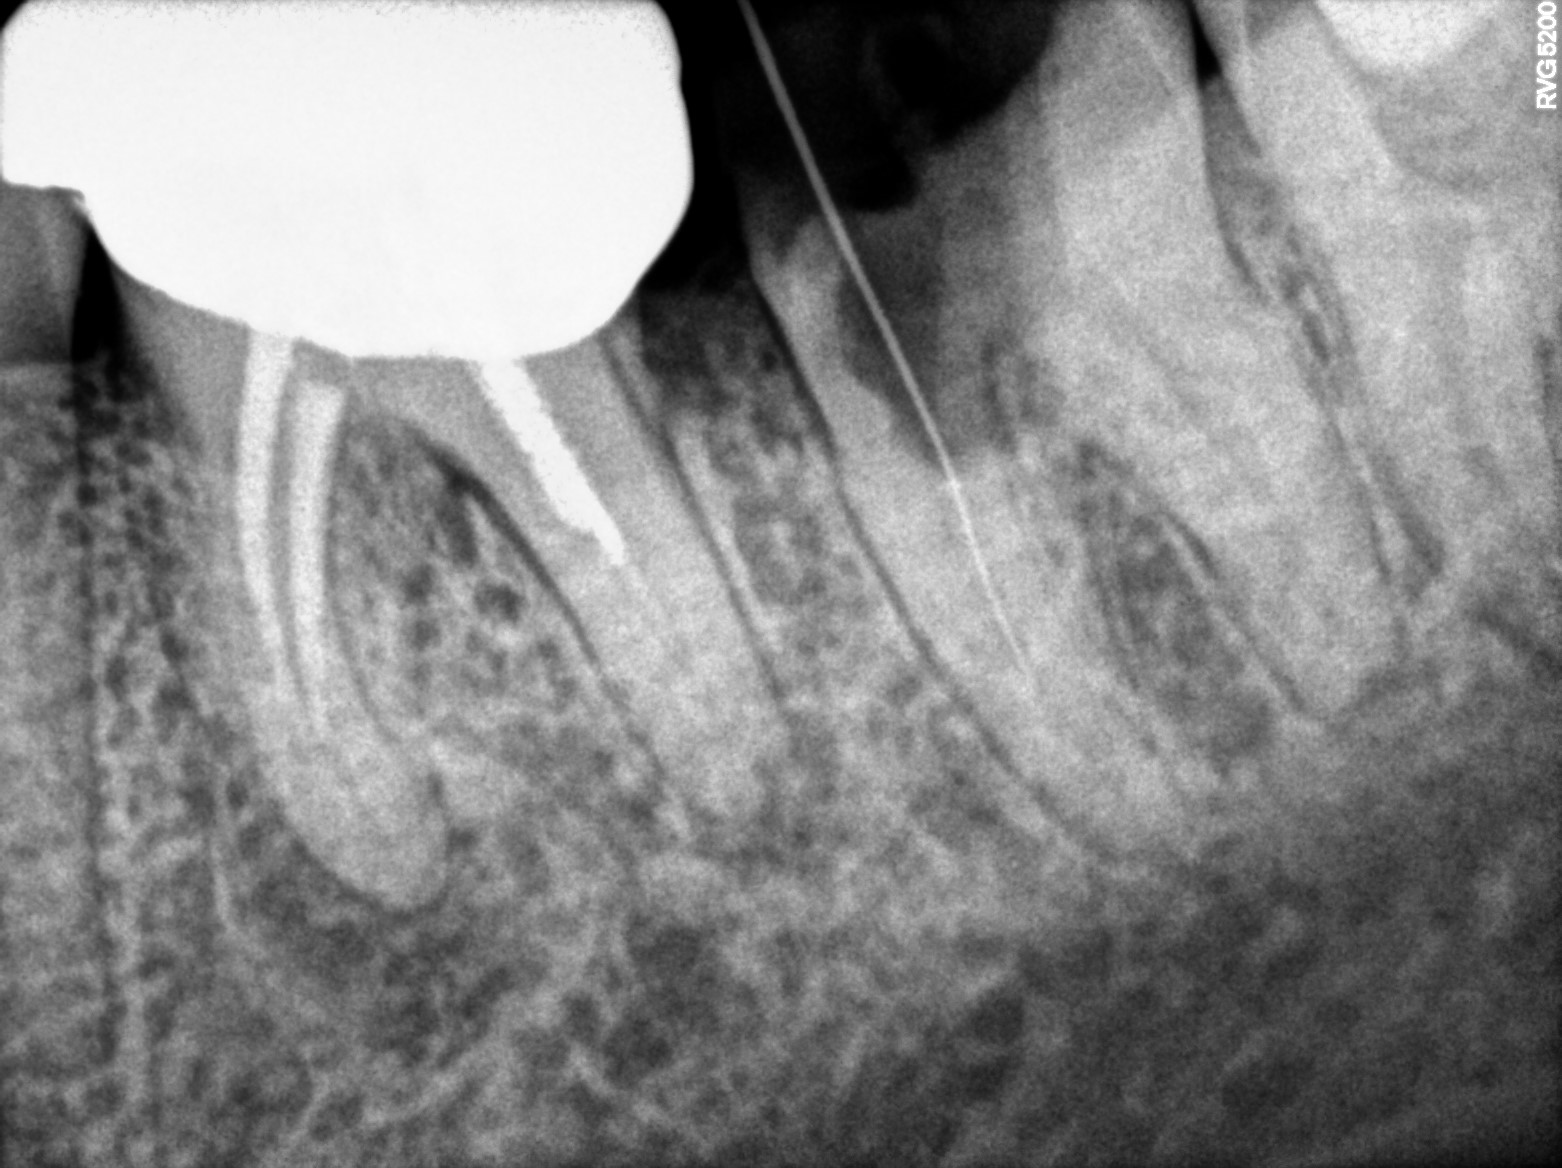

Dental Radiographs FHIR: DocumentReference · LOINC 24641-7

R55.jpg

24641-7